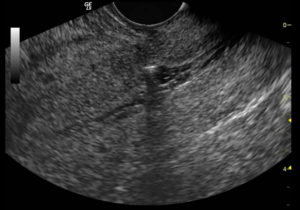

УЗИ матки после кесарева делают перед выпиской из роддома, а потом повторяют через неделю. Для контроля размеров тела и маточной полости используется трансабдоминальный метод – излучатель аппарата помещают на переднюю стенку живота. Если нужно оценить состояние матки или часть шва, то допускается и использование вагинального метода исследования.

Для проверки рубцовой ткани после кесарева УЗИ делают двумя способами. В большинстве случаев состояние матки проверяют через нижнюю часть живота (абдоминально).

Как в клинике делают диагностику матки ультразвуком:

- Пациентка застилает полотенцем кушетку. Она ложится на спину, оголив живот.

- На нижнюю часть живота наносится специальный гель.

- Врач водит по коже датчиком и смотрит на изображение, появляющееся на экране.

- После процедуры женщина удаляет с живота остатки геля.

Иногда матку обследуют через влагалище (трансвагинально). В этом случае на прибор надевают презерватив.